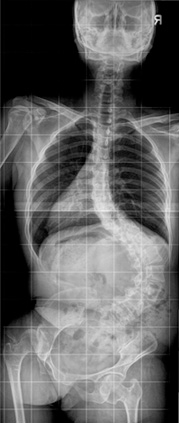

신경근육성척추측만증

수술 전 전신 x-ray 사진